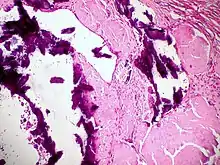

Small bowel duodenum with amyloid deposition Congo red 10X

Small bowel duodenum with amyloid deposition Congo red 10X Amyloidosis, dystrophic calcification